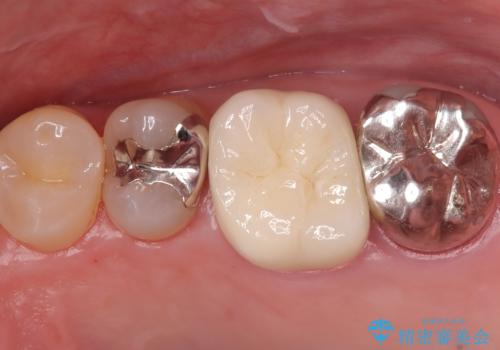

- 患者様は、他院で根管治療を受けていたが、なかなか治らず、より精密な治療を希望して当院を受診されました。マイクロスコープを使用して詳しく診断したところ、上顎第一大臼歯(6番)のMB2(第二頬側根管)の見落としが判明。このままでは感染が残り、再発のリスクが高い状態であるため、当院で精密根管治療を行う方針としました。

マイクロスコープを使用してMB2を確認し、感染源を徹底的に除去。その後、根管内を清掃・消毒し、高品質な充填材で密閉しました。従来の根管治療では見落とされがちなMB2の発見により、治療の精度が大幅に向上し、炎症の改善が期待できる状態となりました。患者様からは「治療後の違和感がなくなり、しっかり噛めるようになった」と喜びの声をいただきました。